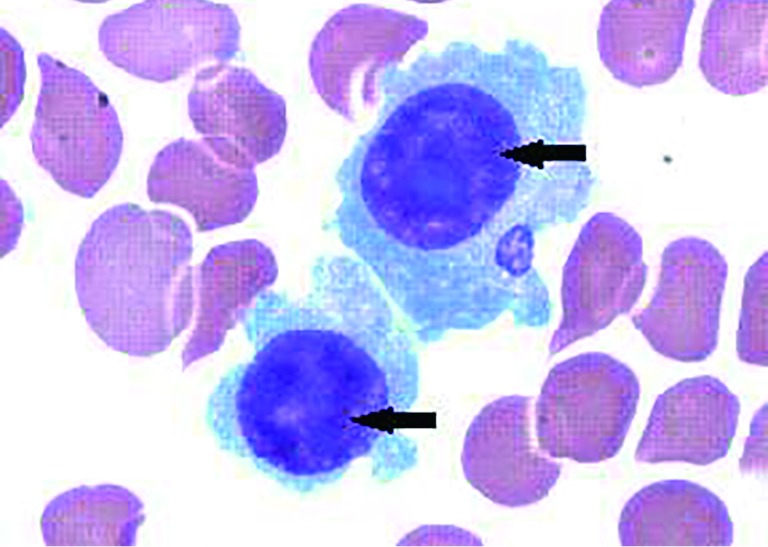

Figure 3.

Video stills of right pleural during thoracoscopy. Multiple nodules of pleural surface (black arrows) and partial lung collapse could be seen.